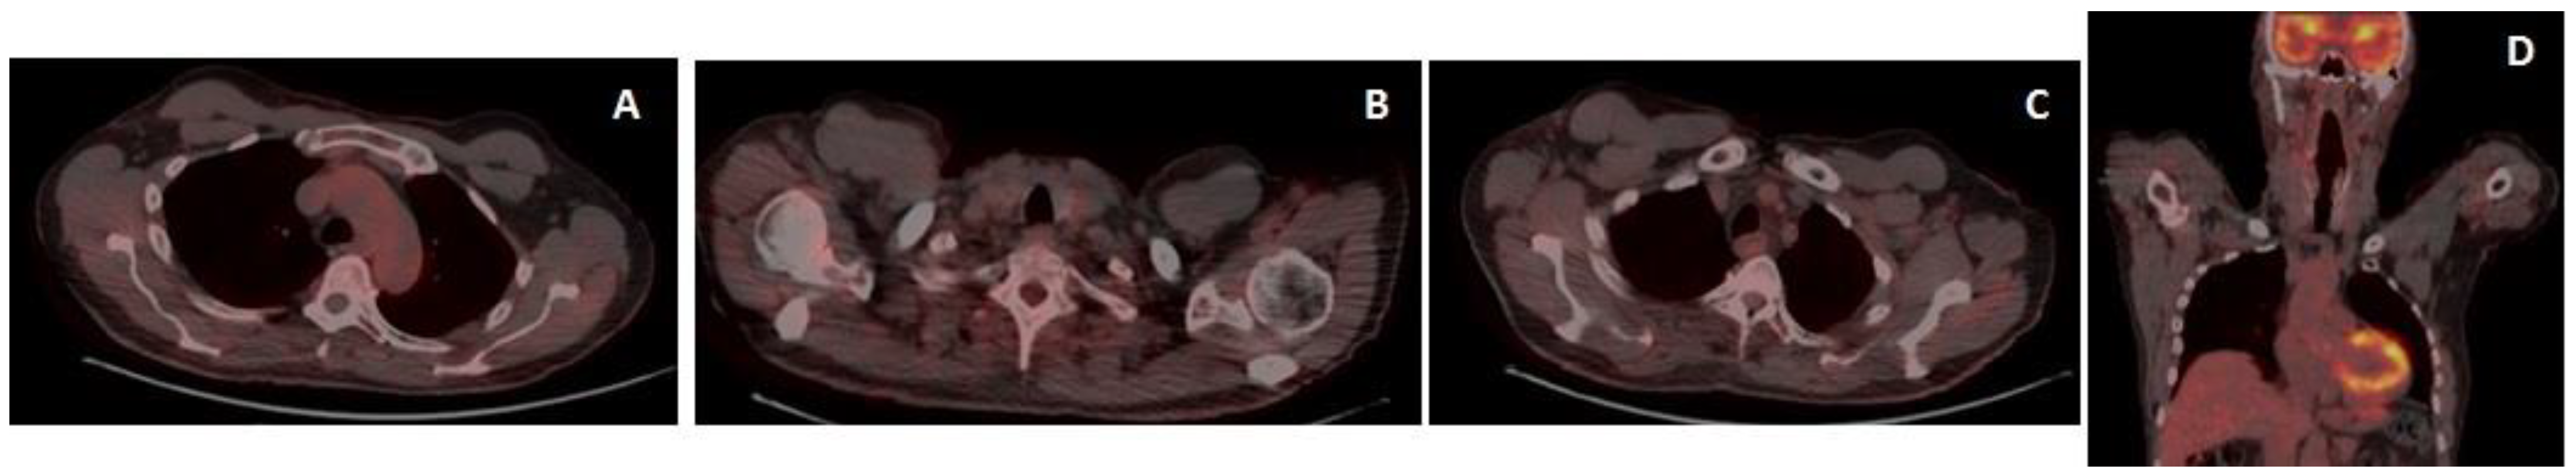

2. Case Report